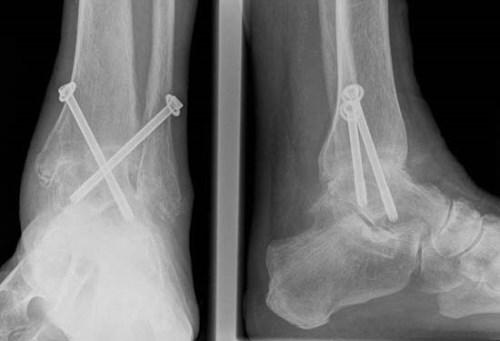

Артодез на этом суставе могут проводить как под общей, так и под спинальной анестезией. Для сращивания могут использовать специальные шурупы, винты, пластины, стержни, костные трансплантаты и другие медицинские приспособления для фиксации.

Также при выполнении артродеза к двум костям могут прикрепляться металлические импланты (винты, стержни, пластины на шурупах и др.). Это делается для того, чтобы удерживать кости в неподвижном положении, благоприятствующем росту новой кости.